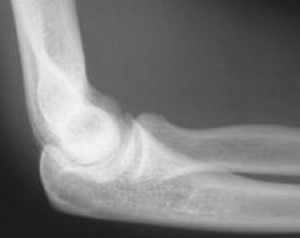

Complete elbow dislocation

A complete elbow dislocation.